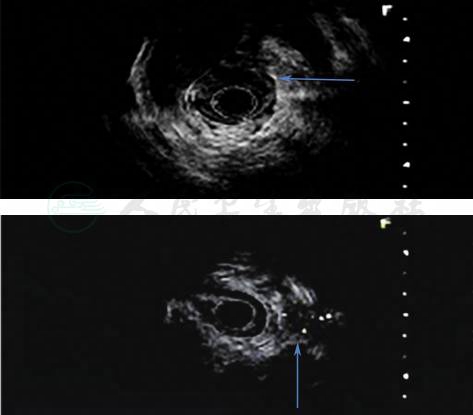

胃镜检查:胃窦隆起性病灶并溃疡形成,胃潴留(图1)。

图1 胃镜检查